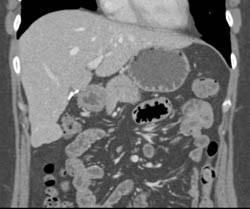

Islet Cell Tail of Pancreas